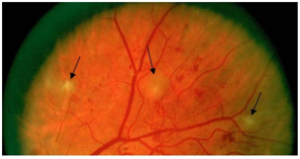

视网膜内微血管异常(IRMA)

视网膜内微血管异常(IRMA)是扭曲扩展的视网膜内血管片段。

视网膜上的点状微血管瘤和视网膜表面清晰可见的新生血管都不属于视网膜内微血管异常。

▲ 视网膜内微血管异常(A)

▲ 视网膜内微血管异常(B)